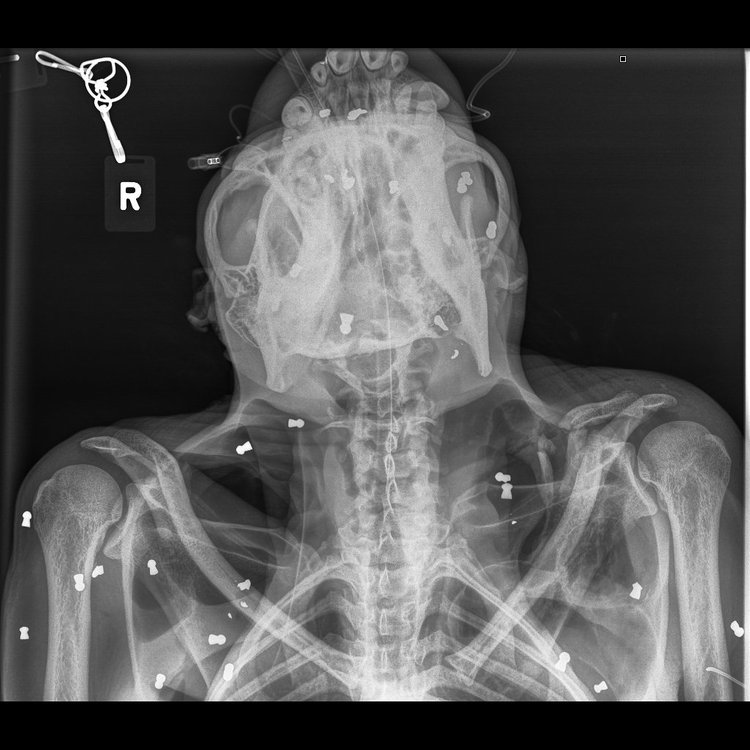

น่าเสียดายลูกลิงที่เรื่องที่อยู่ในสภาพย่ำแย่ได้เสียชีวิตระหว่างทาง และเมื่อทำการตรวจร่างกายแม่ลิงอย่างละเอียดก็พบว่าตลอดร่างกายของมันมีกระสุนตะกั่วที่ยิงจากปืนลม มากถึง 74 เม็ด ! แถมด้วยกระดูกที่หักเพราะถูกตีด้วยของแข็งหลายแห่งมาก แม้แต่ที่กระดูกคอก็หัก แต่มันไม่ตาย

ที่น่าสงสารมากก็คือ ตาของมันทั้งสองข้างมีกระสุนปืนยิงหลายนัดทำให้ตาบอดสนิท (เห็ดชัดในฟิล์ม)